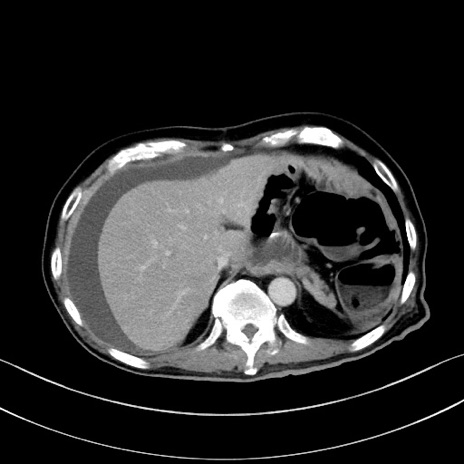

症例28(横断像)

【症例】60歳代男性

【主訴】嘔吐

【現病歴】胃癌にて胃全摘後。食思不振が悪化し、夜中に嘔吐することがある。

【既往歴】胃癌、胃全摘、脾摘、胆摘後

【データ】WBC 5900、CRP 10.56